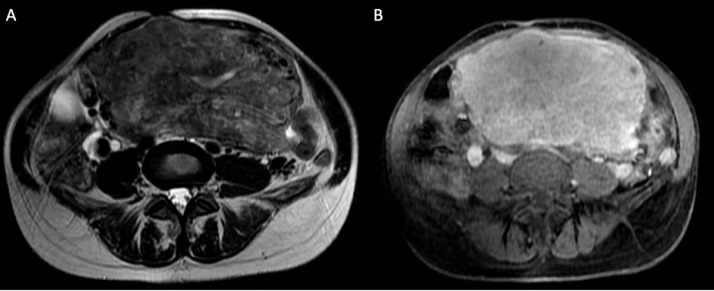

Fig. 2.

MRI axial plane of the uterus. T2-weighted image (A) demonstrates that myometrium is symmetrically expanded by confluent and indistinct leiomyomas. Post-gadolinium fat-suppressed T1-weighted image (B) shows homogeneous enhancement of the uterine nodules.